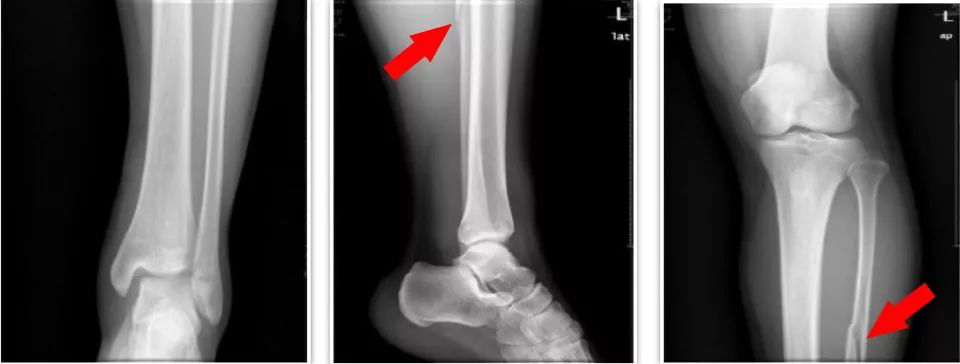

· Maisonneuve 骨折约占踝部损伤的 1%~11%。

损伤机制

多为足处于旋前位时受外旋应力作用,首先致内踝骨折或三角韧带损伤,继而发生下胫腓前韧带及骨间韧带断裂,接着发生高于下胫腓联合水平的腓骨骨折(PER-Ⅲ) ,最后可能出现下胫腓后韧带断裂或后踝骨折而致下胫腓完全分离(PER-Ⅳ),其腓骨的骨折多位于中上 1/3 水平。

内踝骨折或三角韧带损伤

腓骨高位骨折

下胫腓联合损伤